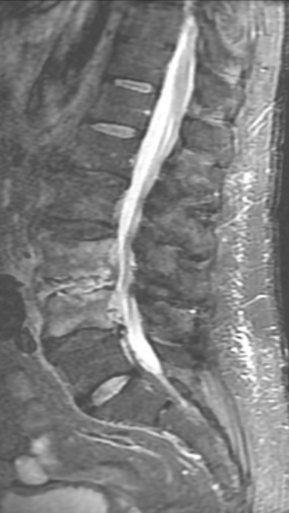

Грыжа Диска L4-L5

3 процедуры ФДТ, 9 процедур MBST

Параметры изменяются в зависимости от процедуры

Дата публикации: 22.08.2025 14:27:20

Спондилодисцит L3 – L4

4 процедуры ФДТ, 9 процедур MBST, 20 процедур ИПМТ

Дата публикации: 22.08.2025 14:27:12